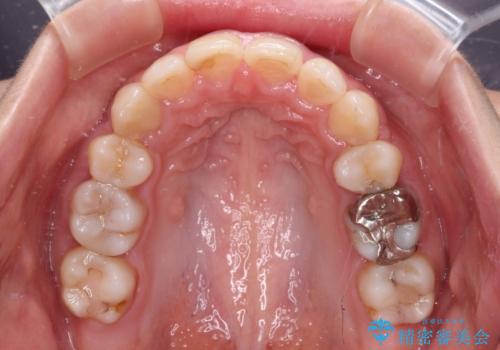

突出した口元が気になる ハーフリンガル装置による抜歯矯正

ハーフリンガルは、通常では表側のワイヤー矯正よりも治療期間がかかります。特に今回のように下顎左側をイレギュラーの第二小臼歯抜歯としたため、さらに時間がかかることが予想されました。

実際に治療をおこなってみると、2年を切る短期間で治療を終えることができました。